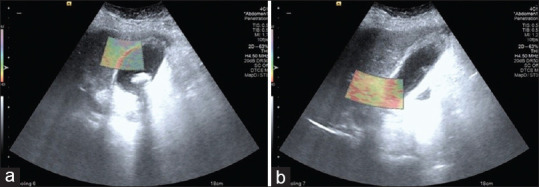

图 3

(a)胆囊结石和胆囊淤泥的超声图像,壁厚 4.5 毫米。 (b) 胆囊底部 VTI 图像,无粘连,胆囊体部有粘连。VTI:虚拟触摸成像